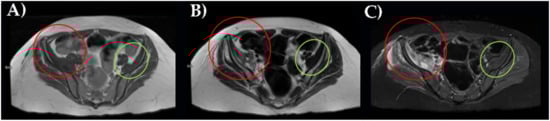

Finally, an MRI examination definitively revealed an iliac right muscle enlargement, hypo and hyperintensity muscle lesions on T2 sequences better seen on fat attenuation sequences (STIR), and partially extending to gluteal muscles group. This is a pattern indicative of muscle hematoma with different lesions at different stages (Figure 2).

Figure 2. MRI of the pelvis with right ileal muscle hematoma performed with a T1- (A), T2- (B), and STIR sequences (C). In red, pathological finding; in green, normal appearance.